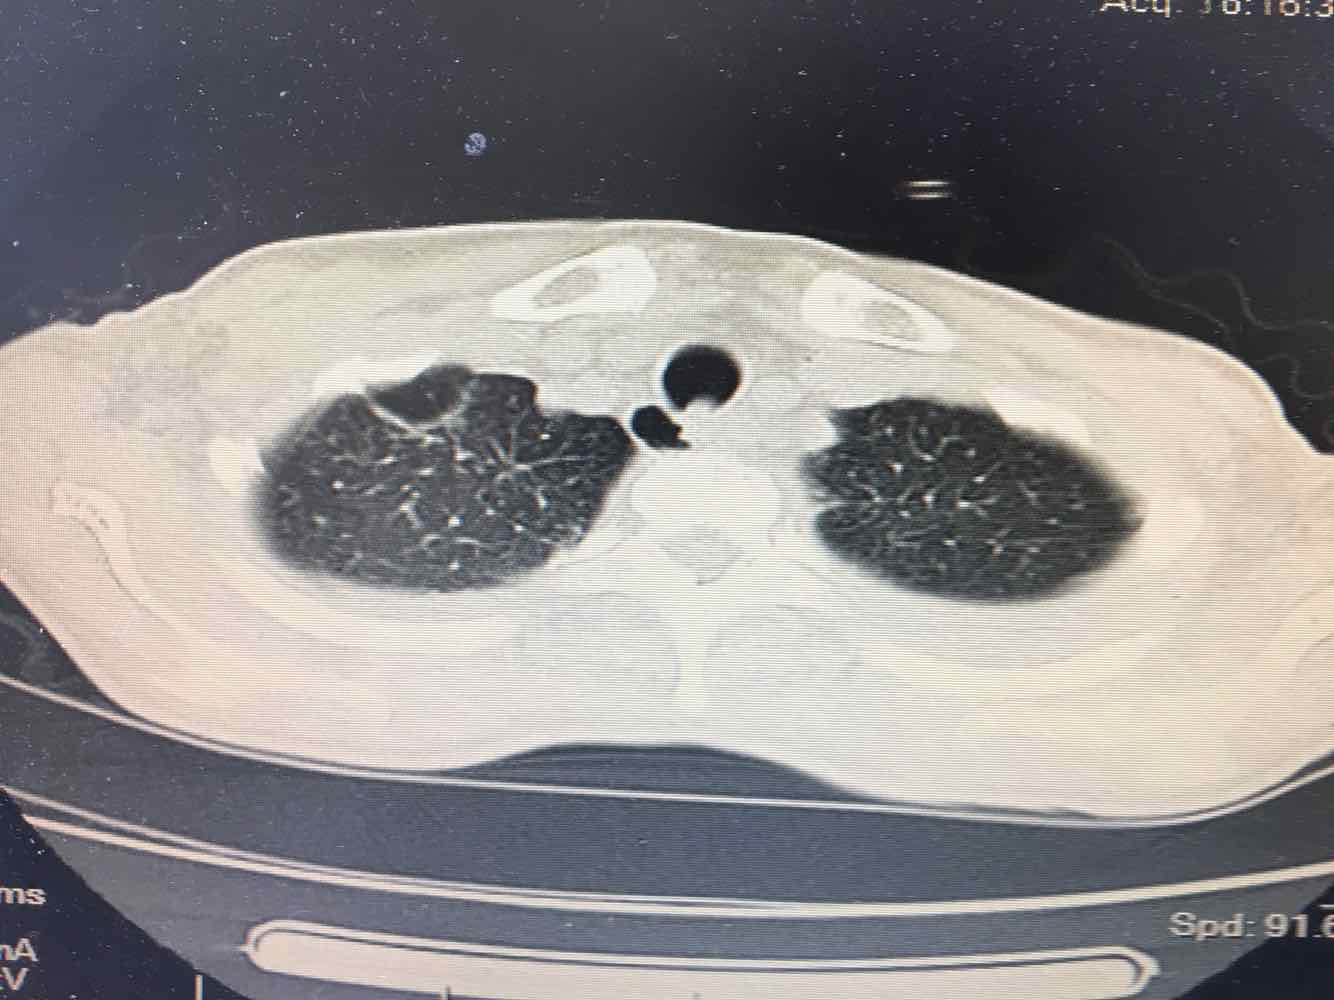

女,51岁,支气管扩张病史多年。慢性咳嗽咳痰喘息30年,加重1个月,无发热,气短为主,痰液不多,上腹不适,少尿。双肺干湿罗音。

图片

1/7

2/7

3/7

4/7

5/7

6/7

7/7